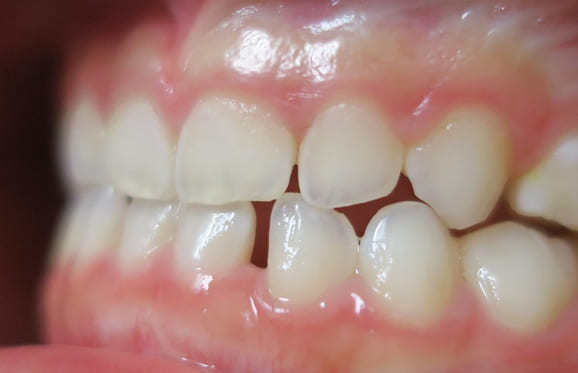

● C4を超え歯根までの虫歯を抜歯、スペースを利用して歯並び全体を整えた症例

藤沢デンタルオフィスの虫歯や破折で抜歯後の部分矯正